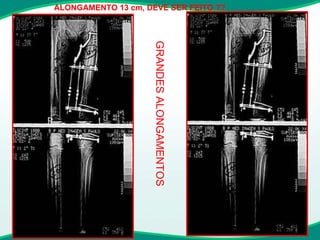

GRANDES ALONGAMENTOS

ALONGAMENTO 13 cm, DEVE SER FEITO ?? GRANDES ALONGAMENTOS